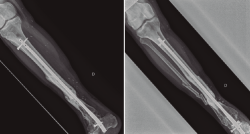

Figura 1. Paciente con fractura del tercio distal de la tibia de tipo Gustilo IIIC que se trató inicialmente con fijador externo.

Figura 2. Pasados 6 meses, se observa ausencia de consolidación de la fractura. El paciente presentaba además supuración de pines distales y clínica infecciosa.